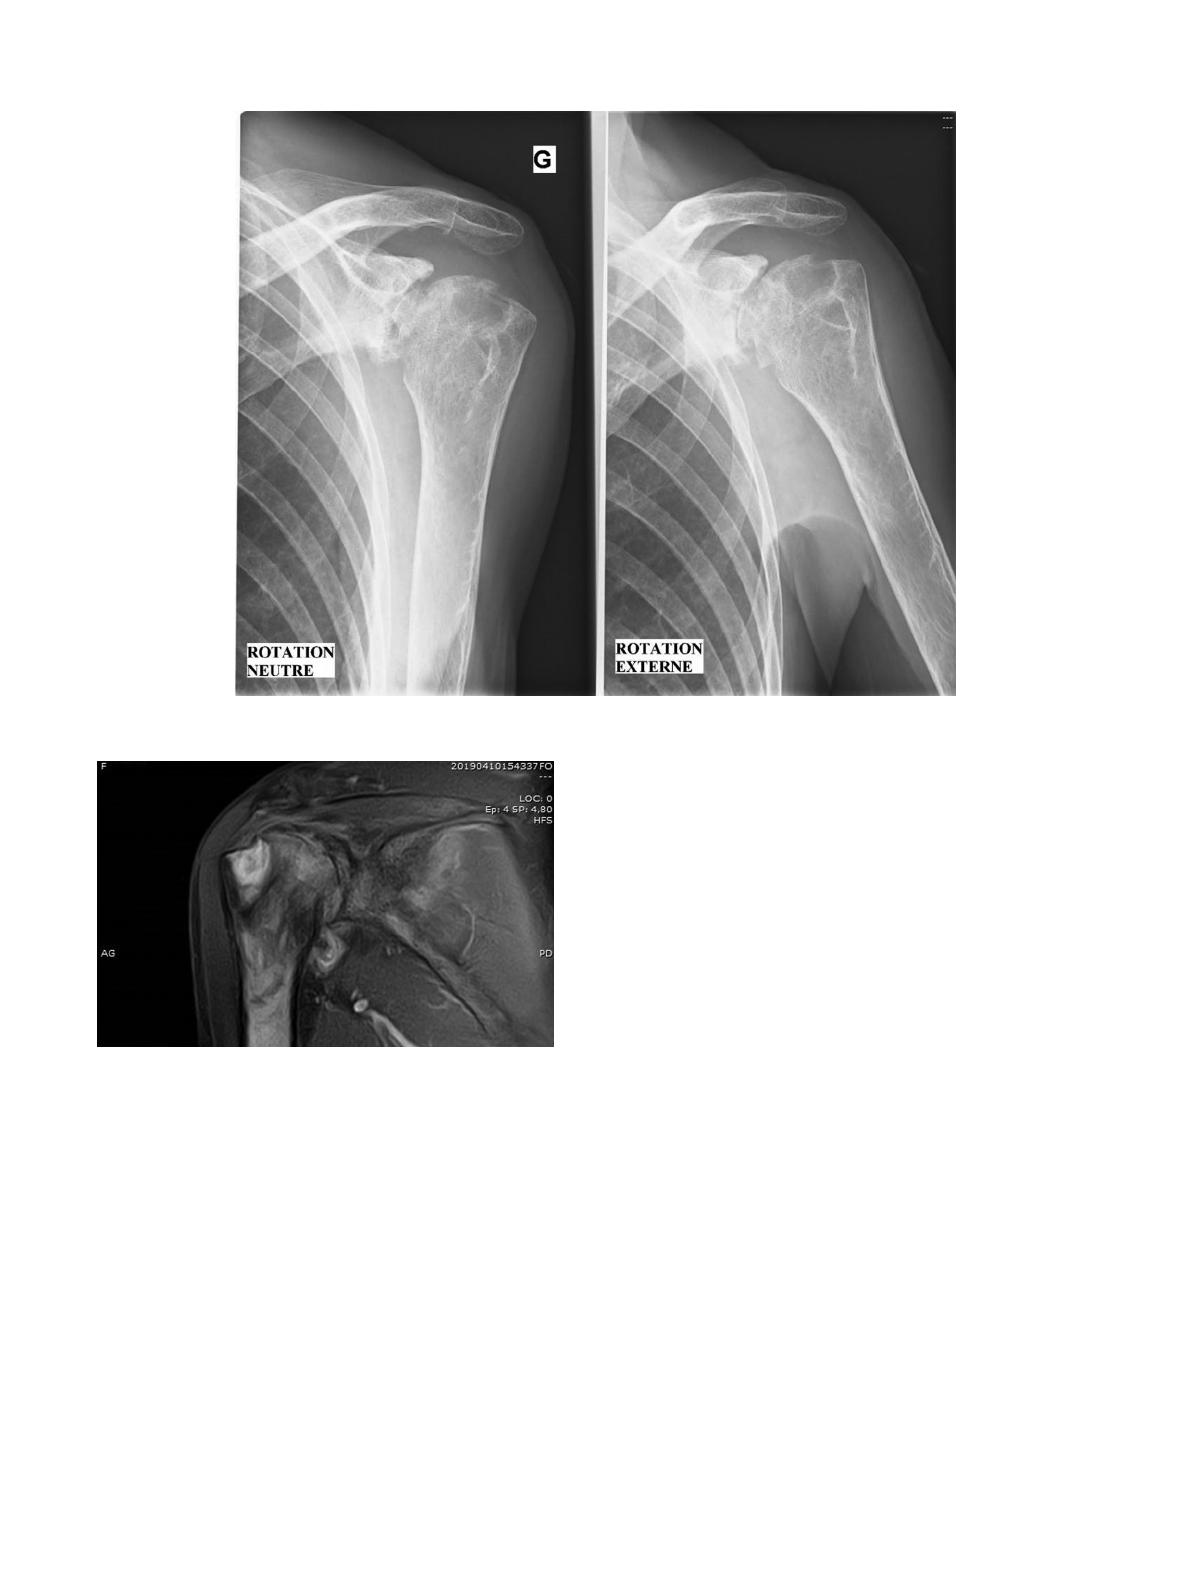

Fig.

1.

Arthrite

tuberculeuse

évoluée

du

poignet.

Les

radiographies

standard

sont

normales

au

départ

ou

montrent

une

arthropathie

pré

existante

(arthrose),

ce

qui

peut

contribuer

à

faire

errer

le

diagnostic

initial.

signes

radio-

graphiques

apparaissent

très

progressivement

:

déminéralisation

osseuse

localisée

puis

plusieurs

mois

plus

tard,

pincement

de

l’interligne

articulaire,

érosions,

géodes,

ostéosclérose,

hyperos-

tose,

calcifications

des

parties

molles

(Fig.

1

et

2).

2.

l’épaule

;

radiographie

standard.

3.

IRM.